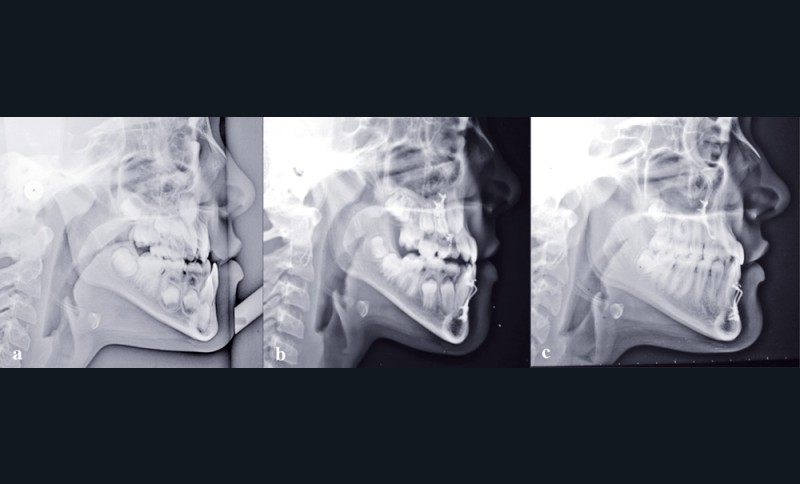

Si l’on analyse le résultat du point de vue squelettique, on constate une belle amélioration orthopédique du prémaxillaire, stable dans le temps. La croissance maxillaire a heureusement été toujours supérieure à la forte croissance mandibulaire. On note après orthopédie un bon support osseux pour la lèvre supérieure qui présente une meilleure épaisseur. À la fin de la croissance, les courbures naso-labiale et labio-mentonnière sont optimisées (fig. 5).

Les téléradiographies de profil confirment la croissance du maxillaire avec une légère tendance rotationnelle antérieure et une avancée du point A de 8 mm. La croissance mandibulaire est homothétique sauf dans la région du point B où elle est freinée (fig. 6-7).